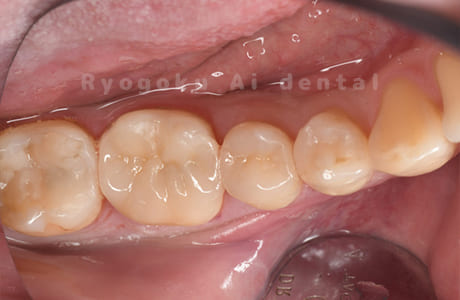

Case27

-

- 原因

- インレー2次カリエス

- 治療内容

- セラミックインレー修復、ダイレクトボンディング

- 治療費用

- 220,000円

銀歯を白くしたい、とのことでご来院された患者様です。

<リスク・副作用>

過度の咬合や衝撃で割れることがあります。術後は痛み、腫れ、痺れなどの副作用が生じる場合があります。

また、ダイレクトボンディングは強い衝撃などにより欠けたりすることがある。経年的に劣化(変色)してくる可能性がある。